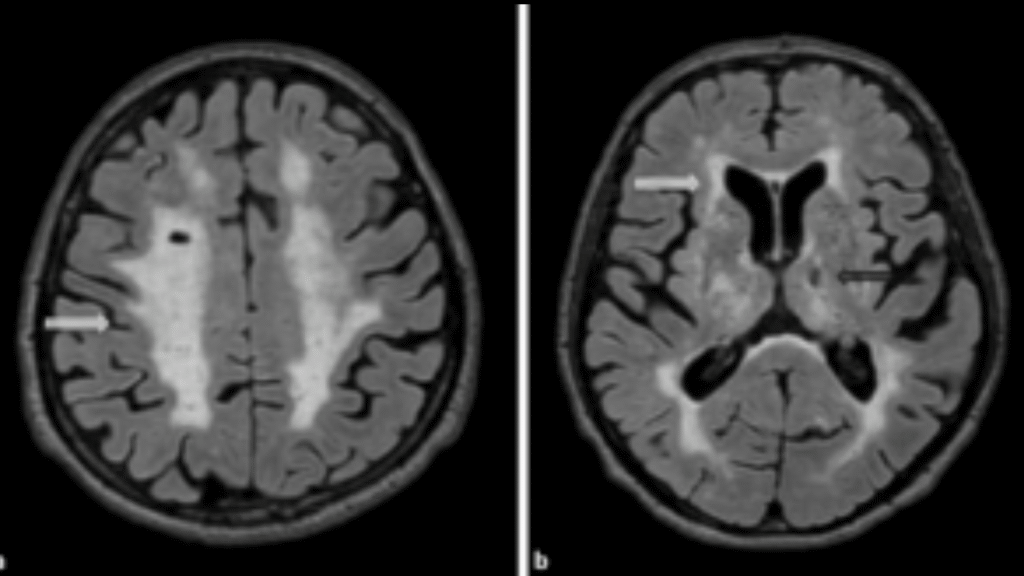

Magnetic Resonance Imaging Predictors of Atrial Fibrillation in Cryptogenic Stroke Cases

Understanding the origin of an ischemic stroke is key in both providing effective treatment and in implementing protective measures to avoid recurrence of stroke. Approximately 25% of ischemic strokes are determined to be embolic strokes of unknown source, where it is difficult to determine whether or not the source is cardioembolic (related to an embolus within the heart). Methods such as administration of anticoagulants or long-term cardiac monitoring can be employed in order to help prevent stroke recurrence when the source of the stroke is defined as cardioembolic. It is theorized that a definable imaging pattern with lesions in multiple vascular territories (MVT; multiple areas in the brain) correlates to strokes of cardioembolic origin. This study aims to develop and validate methods for imaging and identifying MVT in order to more accurately identify strokes with likely cardioembolic sources where preventative measures can be implemented to avoid another stroke. Implications of validating this method of identifying an acute brain imaging biomarker include a reduction in secondary stroke rate, death, disability, and healthcare costs.

Funding: Lone Star Stroke Research Consortium